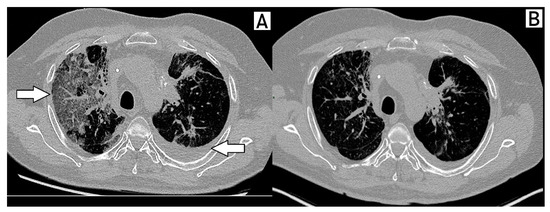

2. Case Description